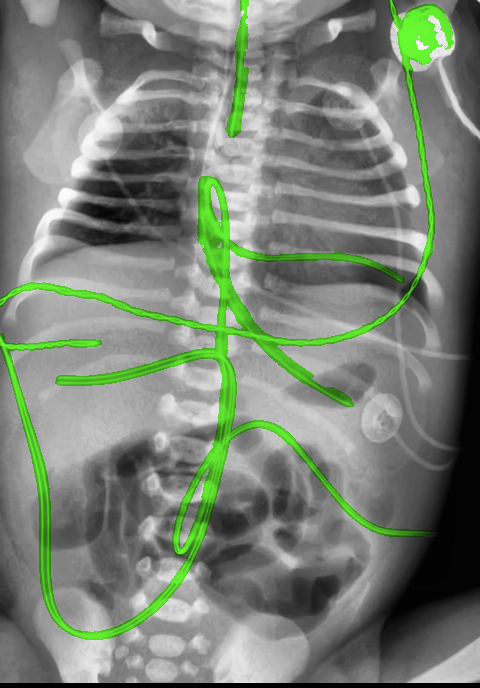

Automated catheter detection is a challenging task. Although most catheters have a radiopaque strip to facilitate detection, the strip may become less apparent depending on the projection angle. Catheters maybe confused by other similar linear structures like ECG leads and anatomy including ribs. Additionally, portions of catheters can be occluded by anatomical structures given that radiographs are a 2D projection of a 3D structure. For example, when a NGT is placed within the oesophagus, the catheter itself becomes less apparent due to the high density of the adjacent vertebrae. Finally, the number and type of catheters that could possibly appear in pediatric X-rays are unknown a priori. The catheters may be intertwined with each other thus making simple line tracing methods fail. Figure 1 gives three sample pediatric X-ray images with some common catheters highlighted in different colors.

To alleviate this annotation problem in catheter detection, we proposed to use X-ray images with simulated catheters by exploiting the fact that catheters are essentially tubular objects with various cross sectional profiles. To be more specific, a synthetic 2D projection of a catheter is generated by first simulating a horizontal catheter profile and then using it as a brush tip to draw along a B-spline path. This generated catheter is then composited with an X-ray image serving as the training data. Another contribution of this work is a segmentation network that can inherently take into account multi-scale information. This network adopts a UNet-style form and contains a recurrent module that can process inputs with increasing scales111Our code is available at https://github.com/xinario/catheter_detection.git.. We have empirically shown that by iterating through the scale space of the input image, higher recall is achieved as compared to using a single scale. Details about the methods are discussed in Section 3. Three sample detection results are shown in Figure 1.

The test dataset is collected locally and only contains frontal chest-abdominal X-rays from patients < 4 weeks old. This is the most common radiograph obtained to confirm placement of catheters such as UACs and UVCs in neonates. Currently, the test set has 35 fully labeled images with different catheter types with sample images previously shown in Figure 1. All the annotated catheters (lines excluding ECG leads) are treated as the same class in the detection.